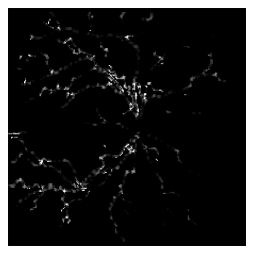

We examine two-dimensional medical images from the Retina [brown2018automated] and X-ray coronary angiogram [app9245507] datasets. Fig. 3 presents these examples with their TCF curvature results. In the curvature images, intensity values indicate curvature, with brighter pixels representing higher values. Also, contrast enhancement is applied for visualization. Gaussian kernels, as explained in (14), are applied to the medical examples using the scale matrix , where is the two-dimensional identity matrix, and .

Retina Images

The left of Fig. 3 shows a sample retinal vessel segmentation image and its curvature results. The segmented retina image includes branching points and vessel segments with different degrees of tortuosity. Branching points occur where a vessel splits into smaller vessels or where multiple vessel segments overlap. Branching points are naturally high-curvature regions because vessels create a cross-shaped structure at these points. We observe this in TCF. Since retinal vessels originate around the optic disc, many branching points appear in this region, where we observe high curvature values. The vessel segments on the left of the image have high tortuosity, whereas the segments on the right are almost flat. The curvature image shows higher values for tortuous vessel segments compared to other segments, demonstrating that TCF captures the tortuosity of retinal blood vessels.

See Section 3.1.3 for a detailed analysis of retina images with ROP categories and an explanation of why centerline methods fail to capture vessel structures.